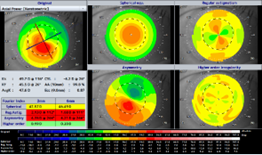

角膜形状解析で得られる情報から、角膜不正乱視の検出(フーリエ解析)や円錐角膜スクリーニングおよびその進行解析(トレンド解析)、あるいはハードコンタクトレンズのベースカーブの推奨値を提供します。